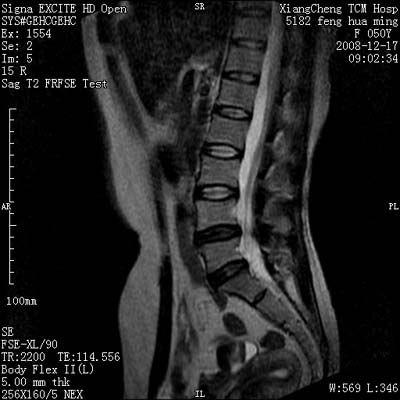

患者,女,50岁,左侧腹股沟及其下方疼痛、酸沉2年。

请各位战友看一下l4-5椎间盘后方椎管内是病灶吗?马尾神经到此处是不是终止了?

腰45椎间盘突出,后部影像可能是硬膜囊粘连引起的

l4/5椎间盘突出。后方硬膜囊受压改变。另外,该病人是否并发子宫肌瘤啊

腰45椎间盘突出,马尾终丝聚集:考虑蛛网膜炎症粘连

l4-5轻突,黄韧带增厚,蛛网膜炎症粘连可能

l4/5椎间盘突出;马尾终丝聚集,考虑蛛网膜炎所致。